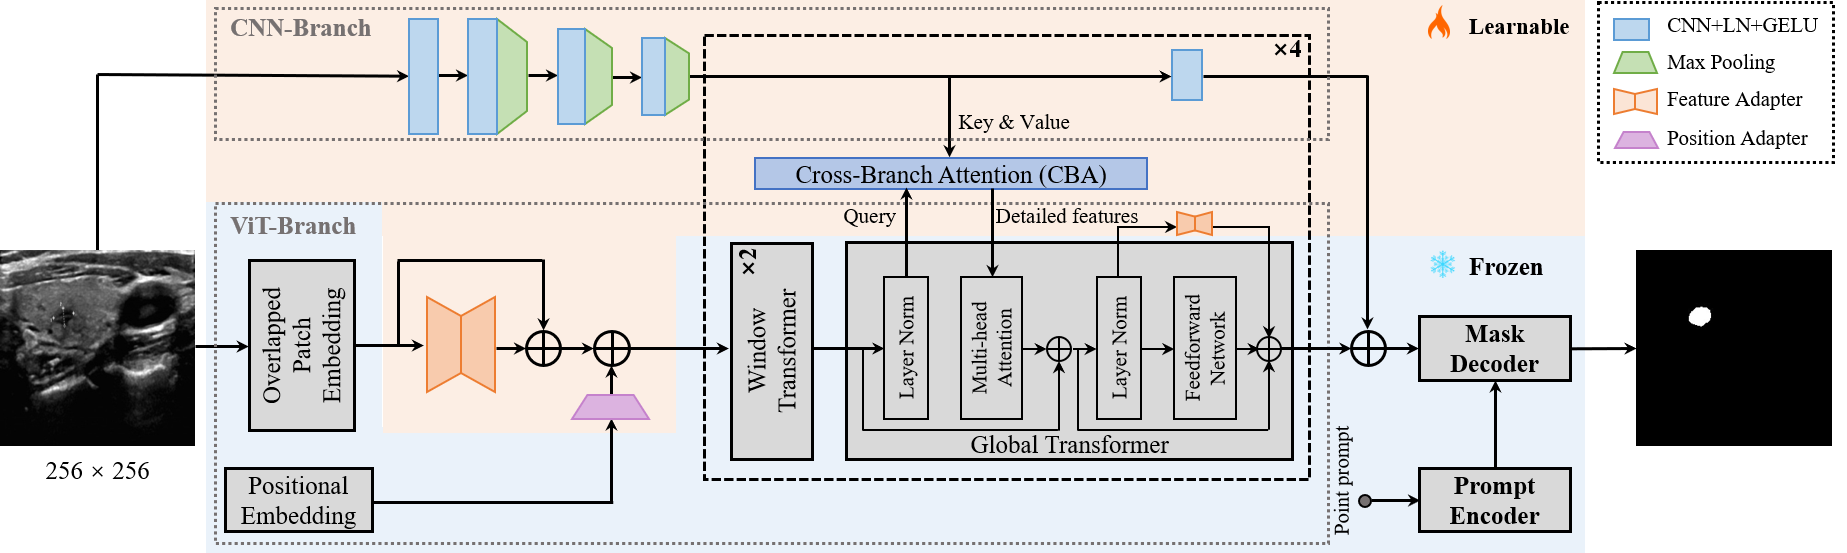

In this paper, we present SAMUS to transfer the exceptional segmentation performance and strong generalization ability of SAM to the domain of medical image segmentation, while reducing computational complexity. SAMUS inherits the ViT image encoder, prompt encoder, and mask decoder of SAM, with tailored designs to the image encoder. First, we shorten the sequence length of the ViT-branch by reducing the input size to lower the computational complexity. Then, a feature adapter and a position adapter are developed to fine-tune the ViT image encoder from natural to medical domains. To complement local (i.e., low-level) information in the ViT image encoder, we introduce a parallel CNN-branch image encoder, running alongside the ViT-branch and propose a cross-branch attention module to enable each patch in the ViT-branch to assimilate local information from the CNN-branch. Furthermore, we construct a large ultrasound dataset called US30K to comprehensively evaluate the efficacy of SAMUS. Experimental results demonstrate that SAMUS outperforms the state-of-the-art methods in both task-specific and universal medical image segmentation. More importantly, SAMUS exhibits remarkable generalization capabilities, while considerably reducing the training cost compared to SAM. The contributions can be summarized as follows:

As depicted in Fig. 8, the overall architecture of SAMUS is inherited from SAM, retaining the structure and parameters of the prompt encoder and the mask decoder without any adjustment. Comparatively, the image encoder is carefully modified to address the challenges of inadequate local features and excessive computational memory consumption, making it more suitable for clinically-friendly segmentation. Major modifications include reducing the input size, overlapping the patch embedding, introducing adapters to the ViT branch, adding a CNN branch, and introducing cross-branch attention (CBA). Specifically, the input spatial resolution is scaled down from pixels to pixels, resulting in a substantial reduction in GPU memory cost due to the shorter input sequence in transformers. The overlapped patch embedding uses the same parameters as the patch embedding in SAM while its patch stride is half to the original stride, well keeping the information from patch boundaries. Adapters in the ViT branch include a position adapter and five feature adapters. The position adapter is to accommodate the global position embedding in shorter sequences due to the smaller input size. The first feature adapter follows the overlapped patch embedding to align input features with the required feature distribution of the pre-trained ViT image encoder. The remaining feature adapters are attached to the residual connections of the feed-forward network in the global transformer to fine-tune the pre-trained image encoder. In terms of the CNN branch, it is parallel to the ViT branch, providing complementary local information to the latter through the CBA module, which takes the ViT-branch features as the query and builds global dependency with features from the CNN branch. It should be noted that CBA is only integrated into each global transformer. Finally, the outputs of both the two branches are combined as the final image feature embedding of SAMUS.

The CNN branch consists of sequentially-connected convolution-pooling blocks. Specifically, the inputs pass through a single convolution block initially, followed by being processed through three convolution-pooling blocks. Then, the feature maps in the CNN branch share the same spatial resolution as those of the ViT branch. In the rest part of the CNN branch, such single convolution blocks are repeated four times in sequence. More details are illustrated in Fig. 8. This minimalist and lightweight design of the CNN branch is to prevent overfitting during training.

3.4 Cross-branch Attention

The cross-branch attention (CBA) module creates a bridge between the CNN branch and the ViT branch to further complement missing local features with the ViT branch. For a pair of feature maps from the ViT branch and the CNN branch , cross-branch attention in the single head can be formulated as:

| (2) |

where represents the Softmax founction. , , and are the learnable weight matrices used to project and to different feature subspaces. is the relative position embedding, and is the dimension of CBA. The final output of CBA is the linear combination of such single-head attention.